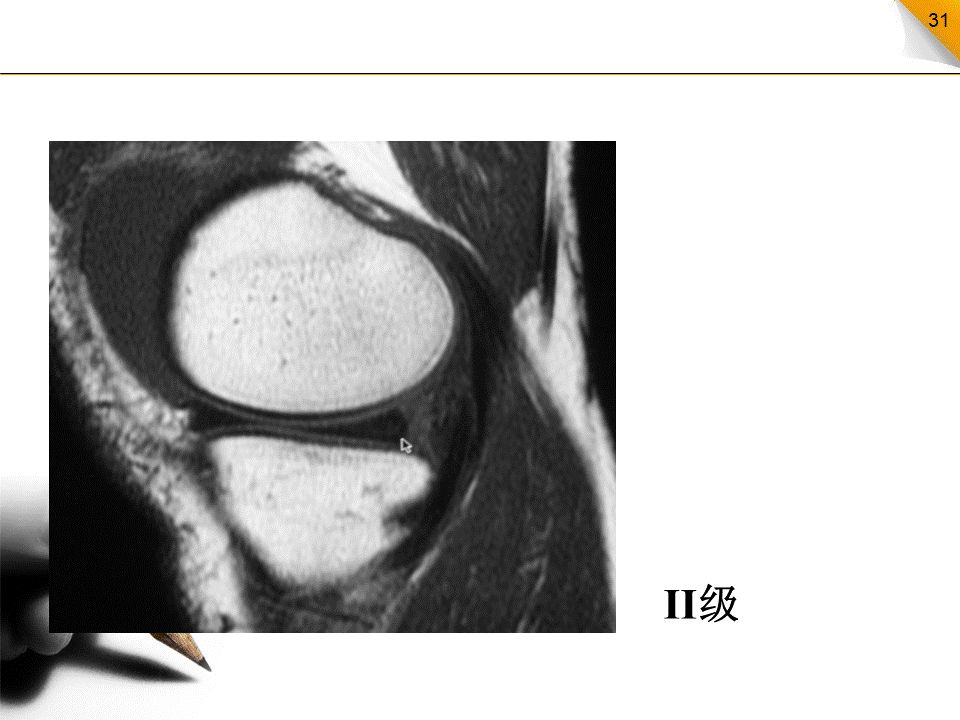

半月板损伤的MR分级

0级:正常半月板,均匀的低信号,形态规则I级:不与半月板关节面相接触的灶性信号增高影II级:半月板内线性信号增高,可延伸至半月板的关节囊缘,但未达到半月板的关节面缘,是I级信号改变的继续,范围更广III级:半月板内的高信号达到半月板的关节面,代表半月板的撕裂IV级:半月板破碎成多块并向关节腔内移位